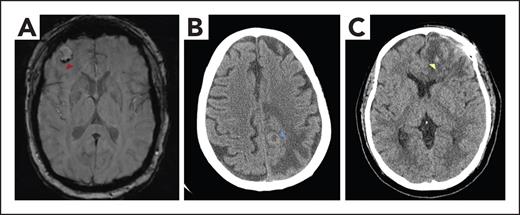

A 52-year-old woman, former smoker with hypertension, was diagnosed with stage IV non–small cell lung cancer (epidermal growth factor receptor wildtype/KRAS wild-type), including several brain metastases. She was treated with brain stereotactic radiosurgery (SRS), as well as carboplatin, pemetrexed, and bevacizumab with systemic response. Three months into the treatment, after mild dyspnea on exertion and hypoxia, a computed tomography (CT) scan chest pulmonary embolism (PE) protocol revealed a new left segmental PE. Bilateral lower extremity venous dopplers showed a new left femoral deep vein thrombosis (DVT). Vital signs were notable for a blood pressure of 133/65 mm Hg, a pulse of 124 beats per minute, a respiratory rate of 18 breaths per minute, and a pulse oximetry reading of 90% on room air. She had a normal neurologic examination. Platelets, renal and hepatic function, partial thromboplastin time (PTT), and prothrombin time (PT) were normal. Echocardiogram did not show right-heart strain. Consult request was as follows: hematology was consulted to assess whether full dose-anticoagulation should be administered in a patient with brain metastases. Hematology assessment was as follows: because the last intracranial imaging was 6 weeks before presentation, she underwent repeat brain magnetic resonance imaging (MRI) with and without contrast, which showed a stable, treated intracranial metastasis with minimal vasogenic edema and mild stable hemosiderin deposition, consistent with chronic minor blood products (Figure 2A). The patient was assessed to have an increased, but not prohibitive, risk of ICH due to hemosiderin deposition and bevacizumab use. Conversely, the brain metastases were considered effectively treated with SRS. Considering her acute symptomatic segmental PE and proximal DVT, therapeutic-dose anticoagulation was started with apixaban 10 mg twice daily for 1 week, followed by 5 mg twice daily. She also continued her anticancer therapy. Surveillance noncontrast CT scan of brain after 48 hours and 2 weeks did not show evidence of ICH.

Imaging of patients with brain tumors with or without ICH. (A) MRI brain axial susceptibility weighted image demonstrating a right frontal brain metastasis with mild peripheral hemosiderin deposition (red arrowhead), consistent with chronic hemorrhage. (B) Noncontrast CT brain axial image revealing a peripherally hyperdense lesion (blue arrowhead) with surrounding confluent hypodensity in the left posterior frontal lobe, consistent with a brain metastasis and vasogenic edema. The hyperdense rim represents high cellularity within the tumor. (C) Noncontrast CT brain axial image showing left frontal postoperative change status after glioblastoma resection, with hypodense vasogenic edema and scattered foci of hyperdensity (yellow arrowhead) consistent with subacute blood products.

A 60-year-old right-handed man with advanced stage IV renal cell carcinoma, receiving first-line nivolumab and cabozantinib for 4 weeks, presented to the emergency room with a first-time focal motor seizure, characterized by right arm and face convulsions lasting 3 minutes. Vital signs, PT, and PTT were normal. Platelets were 85 x 109/L. CT scan of brain without contrast revealed a peripherally hyperdense lesion in the left-frontal lobe, consistent with a brain metastasis, without evidence of acute hemorrhage (Figure 2B). Due to new left-calf edema, bilateral lower extremity venous dopplers revealed new left-calf DVT. CT chest PE protocol demonstrated increased retroperitoneal lymphadenopathy and pulmonary metastases, without evidence of PE. Consult request was as follows: hematology and neurology were consulted to discuss safety of anticoagulation in the setting of newly diagnosed brain metastasis in a patient with renal cell carcinoma at higher risk for ICH. Hematology assessment was as follows: the patient was considered to have an increased risk of anticoagulation-associated ICH due to newly diagnosed renal cell carcinoma brain metastasis as well as thrombocytopenia. The presence of an isolated distal DVT was assessed to be at a low-intermediate risk for progression and PE. Initially prescribed reduced dose of enoxaparin at 0.5 mg/kg twice daily. The patient then underwent SRS for the multiple brain metastases and was discharged home. A noncontrast brain CT scan at 2 weeks did not demonstrate evidence of acute ICH, and the patient remained symptomatic with left-calf edema and pain. Planned surveillance ultrasound doppler did not demonstrate progression of the left-calf DVT. He was transitioned to full-dose enoxaparin 1 mg/kg twice daily with a plan to repeat noncontrast brain CT scan 48 hours later.

A 76-year-old right-handed woman with a left frontal glioblastoma was treated with left frontal craniotomy and subsequent radiation and concurrent temozolomide. Three weeks after completing radiation, she presented to the emergency room with 2 weeks of confusion, progressive aphasia and bilateral lower extremity edema, and weakness. Physical examination was notable for a mild mixed expressive and receptive aphasia, bilateral proximal leg weakness, a wide-based unsteady gait, and right posterior distal thigh and calf tenderness with 2+ pitting edema. Vital signs, platelet count, PT, and PTT were normal. CT brain without contrast revealed increased left frontal vasogenic edema with subacute hemorrhage at the site of the resected tumor (Figure 2C). The neurosurgery consultant did not identify an indication for acute intervention. Bilateral lower extremity venous dopplers demonstrated a DVT in the right femoral, popliteal, and tibial veins. Consult request was as follows: neurology and hematology were consulted to discuss the management of acute right proximal lower extremity DVT in the setting of subacute ICH. Hematology assessment was as follows: a decision was made to place an IVC filter given the standard-higher risk of PE and current contraindication for therapeutic anticoagulation. Because the etiology and acuity of the ICH were not clear, the plan was for a repeat brain MRI and serial noncontrast brain CT to inform the initiation of prophylactic-dose anticoagulation. MRI with and without contrast revealed increased nodular left frontal enhancement, concerning for progressive glioblastoma. CT brain obtained at 72 hours demonstrated stable and resolving ICH. At this stage, prophylactic-dose enoxaparin was started (40 mg once daily). Surveillance CT brain 48 hours later was stable. Her neurological symptoms were improving, and there were no PE symptoms or change in her right leg pain and edema. She was discharged home on enoxaparin 40 mg once daily, with outpatient neurology and hematology follow-up. Figure 3 shows our approach to the management of patients with brain cancer and acute VTE who experienced ICH within the previous 30 days.